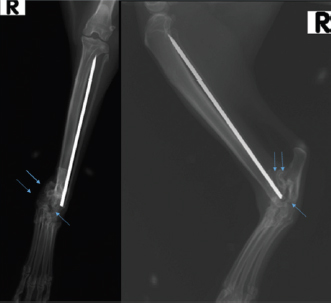

An 18-month-old female stray European cat was referred to the Veterinary Teaching Hospital of the University of Camerino, Italy. Anamnestic data reported a distal tibial epiphyseal sliding fracture (SH1) of the right hind limb inadequately treated 8 months prior with an intramedullary pin by colleagues and consequent chronic tarsocrural instability. Gait evaluation showed a non-weight bearing lameness (grade 4/5) of the right hind limb. An orthopedic examination revealed severe pain during the manipulation of the right tarsus, with bone crackling during stressed manipulation elicited by tibiotarsal joint laxity. Mediolateral and craniocaudal projections of the right tarsus showed failure of the fracture implant (intramedullary pin) caused by an inadequate choice of the apparatus and an incorrect osteosynthesis technique, with a caudomedial displacement of the right distal tibial epiphysis and a moderate process of bone remodeling and resorption (Fig. 1). The patient underwent pantarsal arthrodesis for the recovery of limb functionality. The anesthetic protocol included premedication with 3 μg/kg of dexmedetomidine (Dexdomitor 0.5 mg/ml; Orion Corporation, Finland), 0.3 mg/kg of methadone (Semfortan 10 mg/ml; Dechra, Italy), and 3 mg/kg of ketamine (Ketavet 100; Intervet Productions s.r.l., Italy) administered intramuscularly (IM). General anesthesia was induced with 4 mg/kg of propofol (Fresenius Kabi, Isola della Scala, Italy) administered intravenously (IV) and maintained with oxygen and isoflurane. When a good anesthesia plan was achieved, the femoral–sciatic nerve block was carried out with 0.2 ml/kg of lidocaine (Xylocaine 2%; Zidus Cadila, India). The affected limb and the contralateral foreleg were clipped, and a 4% chlorhexidine gluconate detergent was used for the preliminary preparation of the surgical sites, with a minimum contact time of 5 minutes. The patient was positioned in right lateral recumbency, with the affected limb toward the operating table and the contralateral limb fixed in the abduction position. Cefazolin (Cefazoline Teva; Teva s.r.l., Italy) was administered IV (22 mg/kg) approximately 30 minutes before the skin incision. Under complete aseptic precautions, the craniomedial approach was carried out to expose the tarsal joint. A skin incision, the same length as the plate, was made on the caudomedial aspect of the distal tibia and the craniomedial aspect of the tarsus and proximal metatarsus. The intramedullary pin was removed and sent to the laboratory for bacteriological examination. The tarsocrural, intertarsal, and tarsometatarsal joints were exposed, and the articular cartilage was removed with a high-speed burr. The autologous bone graft was collected from the cancellous bone of the contralateral humerus and was subsequently inserted into the joint spaces. After joint reduction, pantarsal arthrodesis was performed. A 1.2-mm Kirschner wire was driven through the calcaneus into the tibia, and a Compact UniLock 2.0 mandible locking plate (DePuy Synthes, Oberdorf, Switzerland) of 1.5-mm thickness was contoured to achieve the functional angle of tarsus extension and was positioned on the medial surface of the tarsus (Fig. 2). The plate was fixed with ten 2.0 mm locking screws and a cortical screw. The soft tissues were sutured by planes using a USP 3/0 absorbable monofilament thread. No tension at the suture lines was observed. The surgery lasted for 63 minutes. At the end of the surgery, an X-ray examination (Fig. 3) showed a good apposition of the fracture, with a slight internal rotation of the calcaneus; the apparatus seemed adequate, with a total plate screw density (PSD) of 0.85. The joint was fixed at 137° in extension. After radiographic examination, a soft padded bandage was applied for 14 days, which was renewed weekly. As needed, 0.3 mg/kg of methadone (Semfortan 10 mg/ml; Dechra, Italy) was administered IM for 24 hours postoperatively. Anti-inflammatory therapy (meloxicam 0.05 mg/kg; Metacam 40 mg/ml; Boehringer Ingelheim Vetmedica, Germany) and ranitidine (2 mg/kg; Zantadine 30 mg/ml; Ceva s.p.a., Italy) IV were administered on an inpatient basis. The first orthopedic evaluation, the first day after surgery, showed an improvement in gait (grade 2/5 of lameness on walk). The cat was discharged from the hospital after 3 days with a prescription of anti-inflammatory and analgesic therapy. The head of the cat shelter was instructed to subject the cat to cage rest for 30 days. At the first follow-up, 7 days after surgery, the soft padded bandage was renewed, and the cat showed a steady improvement in gait. Fourteen days after surgery, the soft bandage was removed; the orthopedic examination showed mild improvement in gait, although second-degree lameness and an extended tarsal and flexed stifle gait persisted because of the arthrodesis procedure. No swelling or dehiscence at the surgical site or skin tension under the plate was observed; the suture was removed, and the cat was discharged with light exercise on a larger cage recommendation for the remaining 15 days. One month after surgery, at the orthopedic evaluation, the head of the cat shelter reported a slight worsening of lameness after a sharp jump had occurred 7 days prior. The patient showed good limb function, with a slight worsening of gait during the trot, and the radiographic evaluation showed good bone activity, with 50%–66% of the joint fusion and fracture healed, although a metatarsal stress fracture was revealed (Fig. 4). Four months after surgery, radiographs revealed stable implants and an almost complete fusion of the joints (Fig. 5). The surgical wound site, 30 and 120 days after surgery, healed very well, with an efficient aesthetic result of the limb, even with a slight loss of skin elasticity, which occurs naturally after surgery. The patient never showed discomfort at the implant site, even though the plate was very superficial and palpable under the thin skin (Fig. 6). Moderate free activity with gradual introduction to freedom in the feline colony was prescribed.

Fig. 4. Radiographic follow-up examination 4 weeks after pantarsal arthrodesis revealing a near fusion of the arthrodesis and a fracture of the second metatarsus.